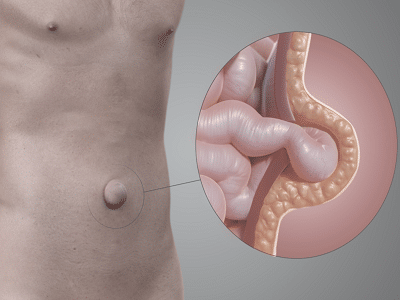

Es una de las preocupaciones más comunes que experimentan los pacientes meses o incluso años después de haberse sometido a una intervención: siento la malla. En la consulta en Costa Rica, recibo con frecuencia a personas que se alarman al notar un pinchazo sutil, una sensación de entumecimiento o la percepción de un “cuerpo extraño” […]